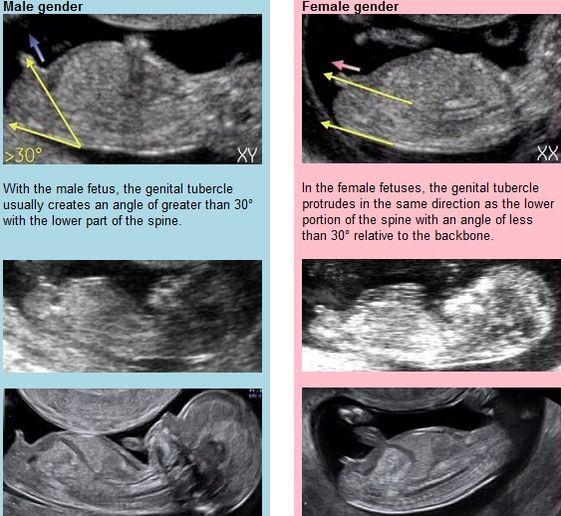

Vím, že to ještě není jisté a že si mám počkat... Jen mě zajímají Vaše tipy a zkušenosti, co by to mohlo podle Vás být 😊 našla jsem i fotku, jak se údajně pohlaví určuje, ale jsem z toho pořád dost nejistá 😁

Dost mě matou ty určení podle toho, jak jde hrbolek nahoru, ale stejně to vidím na toho kluka 😁

Me prijde ze hrbolek teda nesmeruje uplne nahoru ale je vice podobny ruzovemu clanku tak za me si myslim ze holcicka🙂

No podle toho návodu to fakt vypadá spíš na holku. Ale bůhví co je na tom pravdy 😊